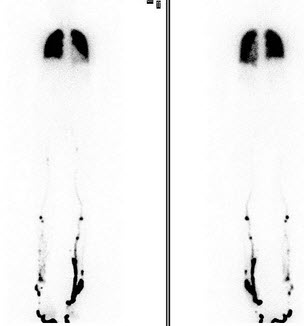

25、单项选择题

一患者静息99Tcm-MIBI心肌灌注显像如图,诊断是()

A.急性心尖前壁、间壁心肌梗死

B.心尖、前壁、间壁陈旧性心肌梗死

C.心尖、前壁、间壁梗死

D.梗死区无存活心肌

E.以上都不是

点击查看答案